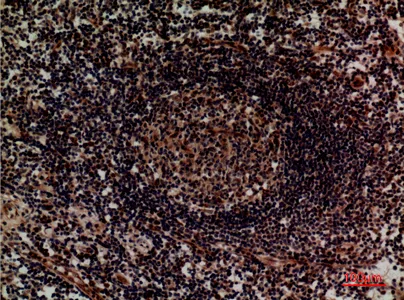

Fractalkine Receptor Rabbit Polyclonal Antibody

Cat: APRab00484

Size1:50μL Price1:$150

Size2:100μL Price1:$280

Size3:500μL Price1:$280

Application:WB,IHC-P,ELISA

Reactivity:Human,Mouse,Rat

Conjugate:Unconjugated

Gene Name:CX3CR1

Size2:100μL Price1:$280

Size3:500μL Price1:$280

Application:WB,IHC-P,ELISA

Reactivity:Human,Mouse,Rat

Conjugate:Unconjugated

Gene Name:CX3CR1